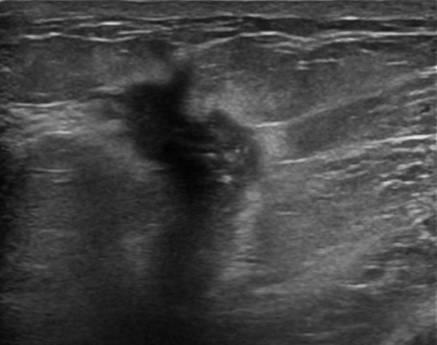

Ung thư vú

» Thông tin: Nữ giới – 55 tuổi.

» Lâm sàng: Khối tuyến vú.